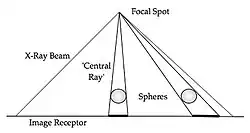

- It is found that the smaller this source, the better is the spatial resolution in the recorded radiograph. The reason can be appreciated from Figure 3.11, where it is seen that a focal spot of finite size, f, on the anode target of the X-ray tube (XRT) is used to expose the edge of a opaque object. The image of the edge is seen to be spread out into a penumbra, p, of dimensions depending on the ratio of the distance from the X-ray source to the image (the SID) and the distance from the X-ray source to the object. This ratio is called the Geometric Magnification, m. It is equivalent, on the basis of considering the geometry of this arrangement, to the image size divided by the object size.

Fig. 3.13: Radiographic distortion in the imaging of two spheres.

- It should also be appreciated that the beam emerging from a focal spot is shaped by rectangular collimators so that a divergent, rectangular radiation field strikes the patient. We can therefore infer that objects in the peripheral regions of the field will experience a greater magnification and resultant distortions in shape relative to those in the beam’s centre. We can also infer that these effects should increase as we move from the centre of the field to the periphery of the radiation field.

- The unequal magnification effects are illustrated in Figure 3.13. The divergent nature of the X-ray beam can be seen to cause shadows of peripheral disk-shaped objects to become broadened and distorted. The situation in wrist radiography is illustrated in Figure 3.14. Here, the ‘Central Ray’ of the X-ray beam was centered near the trapezium bone and the image represents differences between true anatomical locations and those imaged. It is seen that the best match occurs, as expected, in the region of the Central Ray and that the mismatch increases as we move towards the more peripheral regions of the body part.